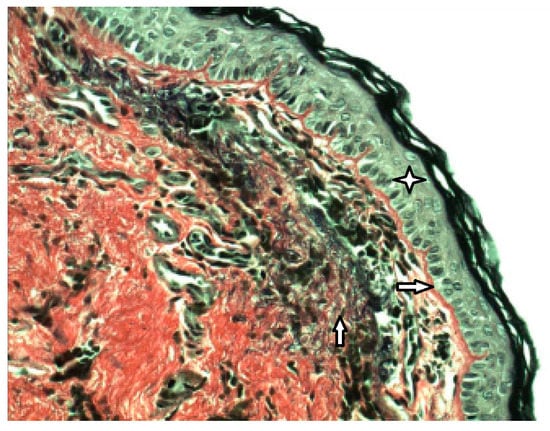

External epithelial layer,

Basal membrane,

Fragmented elastic fibers in the middle layer.